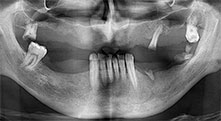

Bratu: Utilizamos los insertos de forma rutinaria para la extracción de injertos óseos y la ranuración de las crestas alveolares. También utilizamos las Piezomed B6/B7 para practicar osteotomías en dientes retenidos y no retiramos implantes que pueden conservarse. Todas estas son indicaciones que requieren cortes profundos y limpios.

Bratu: Nos gusta utilizar la técnica de sándwich para realizar aumentos en la cara lateral del maxilar inferior. En este procedimiento, se utiliza la sierra piezoquirúrgica para preparar una tapa ósea, mientras que el fragmento crestal se fija con microtornillos. Entre medias, colocamos una combinación de hueso autólogo y material óseo adicional xenógeno. Y con ello obtenemos un rendimiento muy fiable. Asimismo, en los ranurados de la cresta alveolar del maxilar inferior, nunca se puede prescindir de cortes verticales suficientemente dimensionados, pues, de lo contrario, los huesos pueden fracturarse fácilmente.